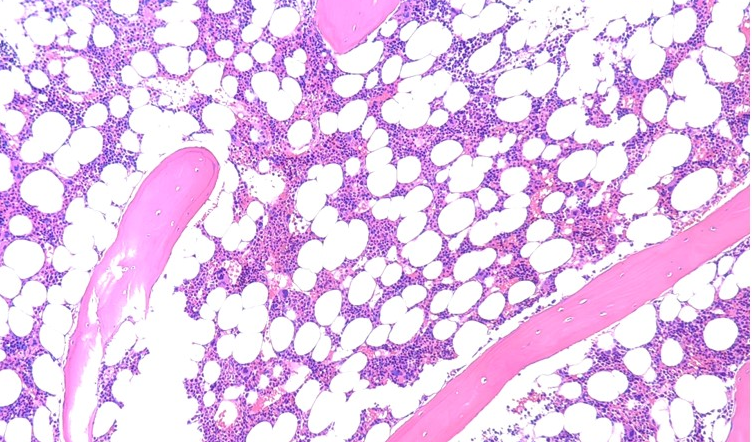

Bone marrow: Generates naïve B lymphocytes. Red marrow (in flat, irregular bones and epiphyses of long bones) consists of hematopoietic tissue and blood sinusoids; yellow marrow is fat-rich but retains hematopoietic potential.

| Central | Bone marrow | Hematopoietic stem cell | CD34, CD117 | CD45 | Identify HSCs, trace differentiation |

| Immature B cell | CD19, CD20 | CD45R | Assess B-cell maturation | ||

| NK-cell progenitor | CD56, CD16 | CD3⁻ | Track NK differentiation | ||